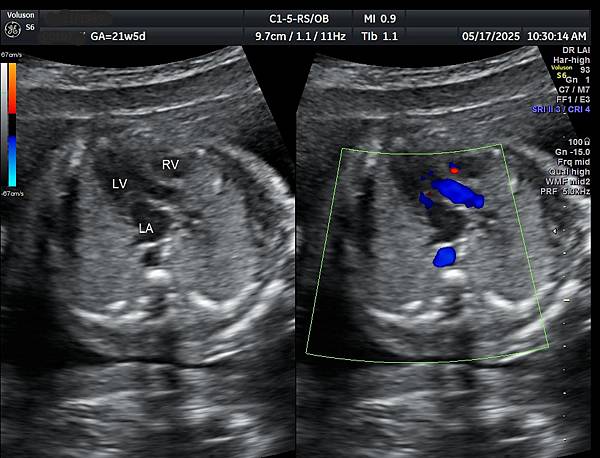

2026年1月9日一位34歲第三胎懷孕21週又6天的孕婦在孕兒診所接受胎兒心臟及高層次超音波檢查,檢查後除了邊緣型前置胎盤、羊水指數正常偏少( AFI: 8.19 cm )之外,沒有異常發現。

孕婦告訴我們第二胎(2024年10月)也是在孕兒診所檢查,因為胎兒心臟檢查出胎兒有血管環(附圖1,動脈導管在氣管右側,主動脈弓在氣管左側,參考第446篇文章),建議抽羊水做晶片檢查,結果胎兒是狄喬治症候群( 附圖 2. ),當年她已抽24000元的NIPS( 附圖 3.)沒有異常發現(包含狄喬治症候群),這一胎她直接抽羊水,還好檢查結果正常。